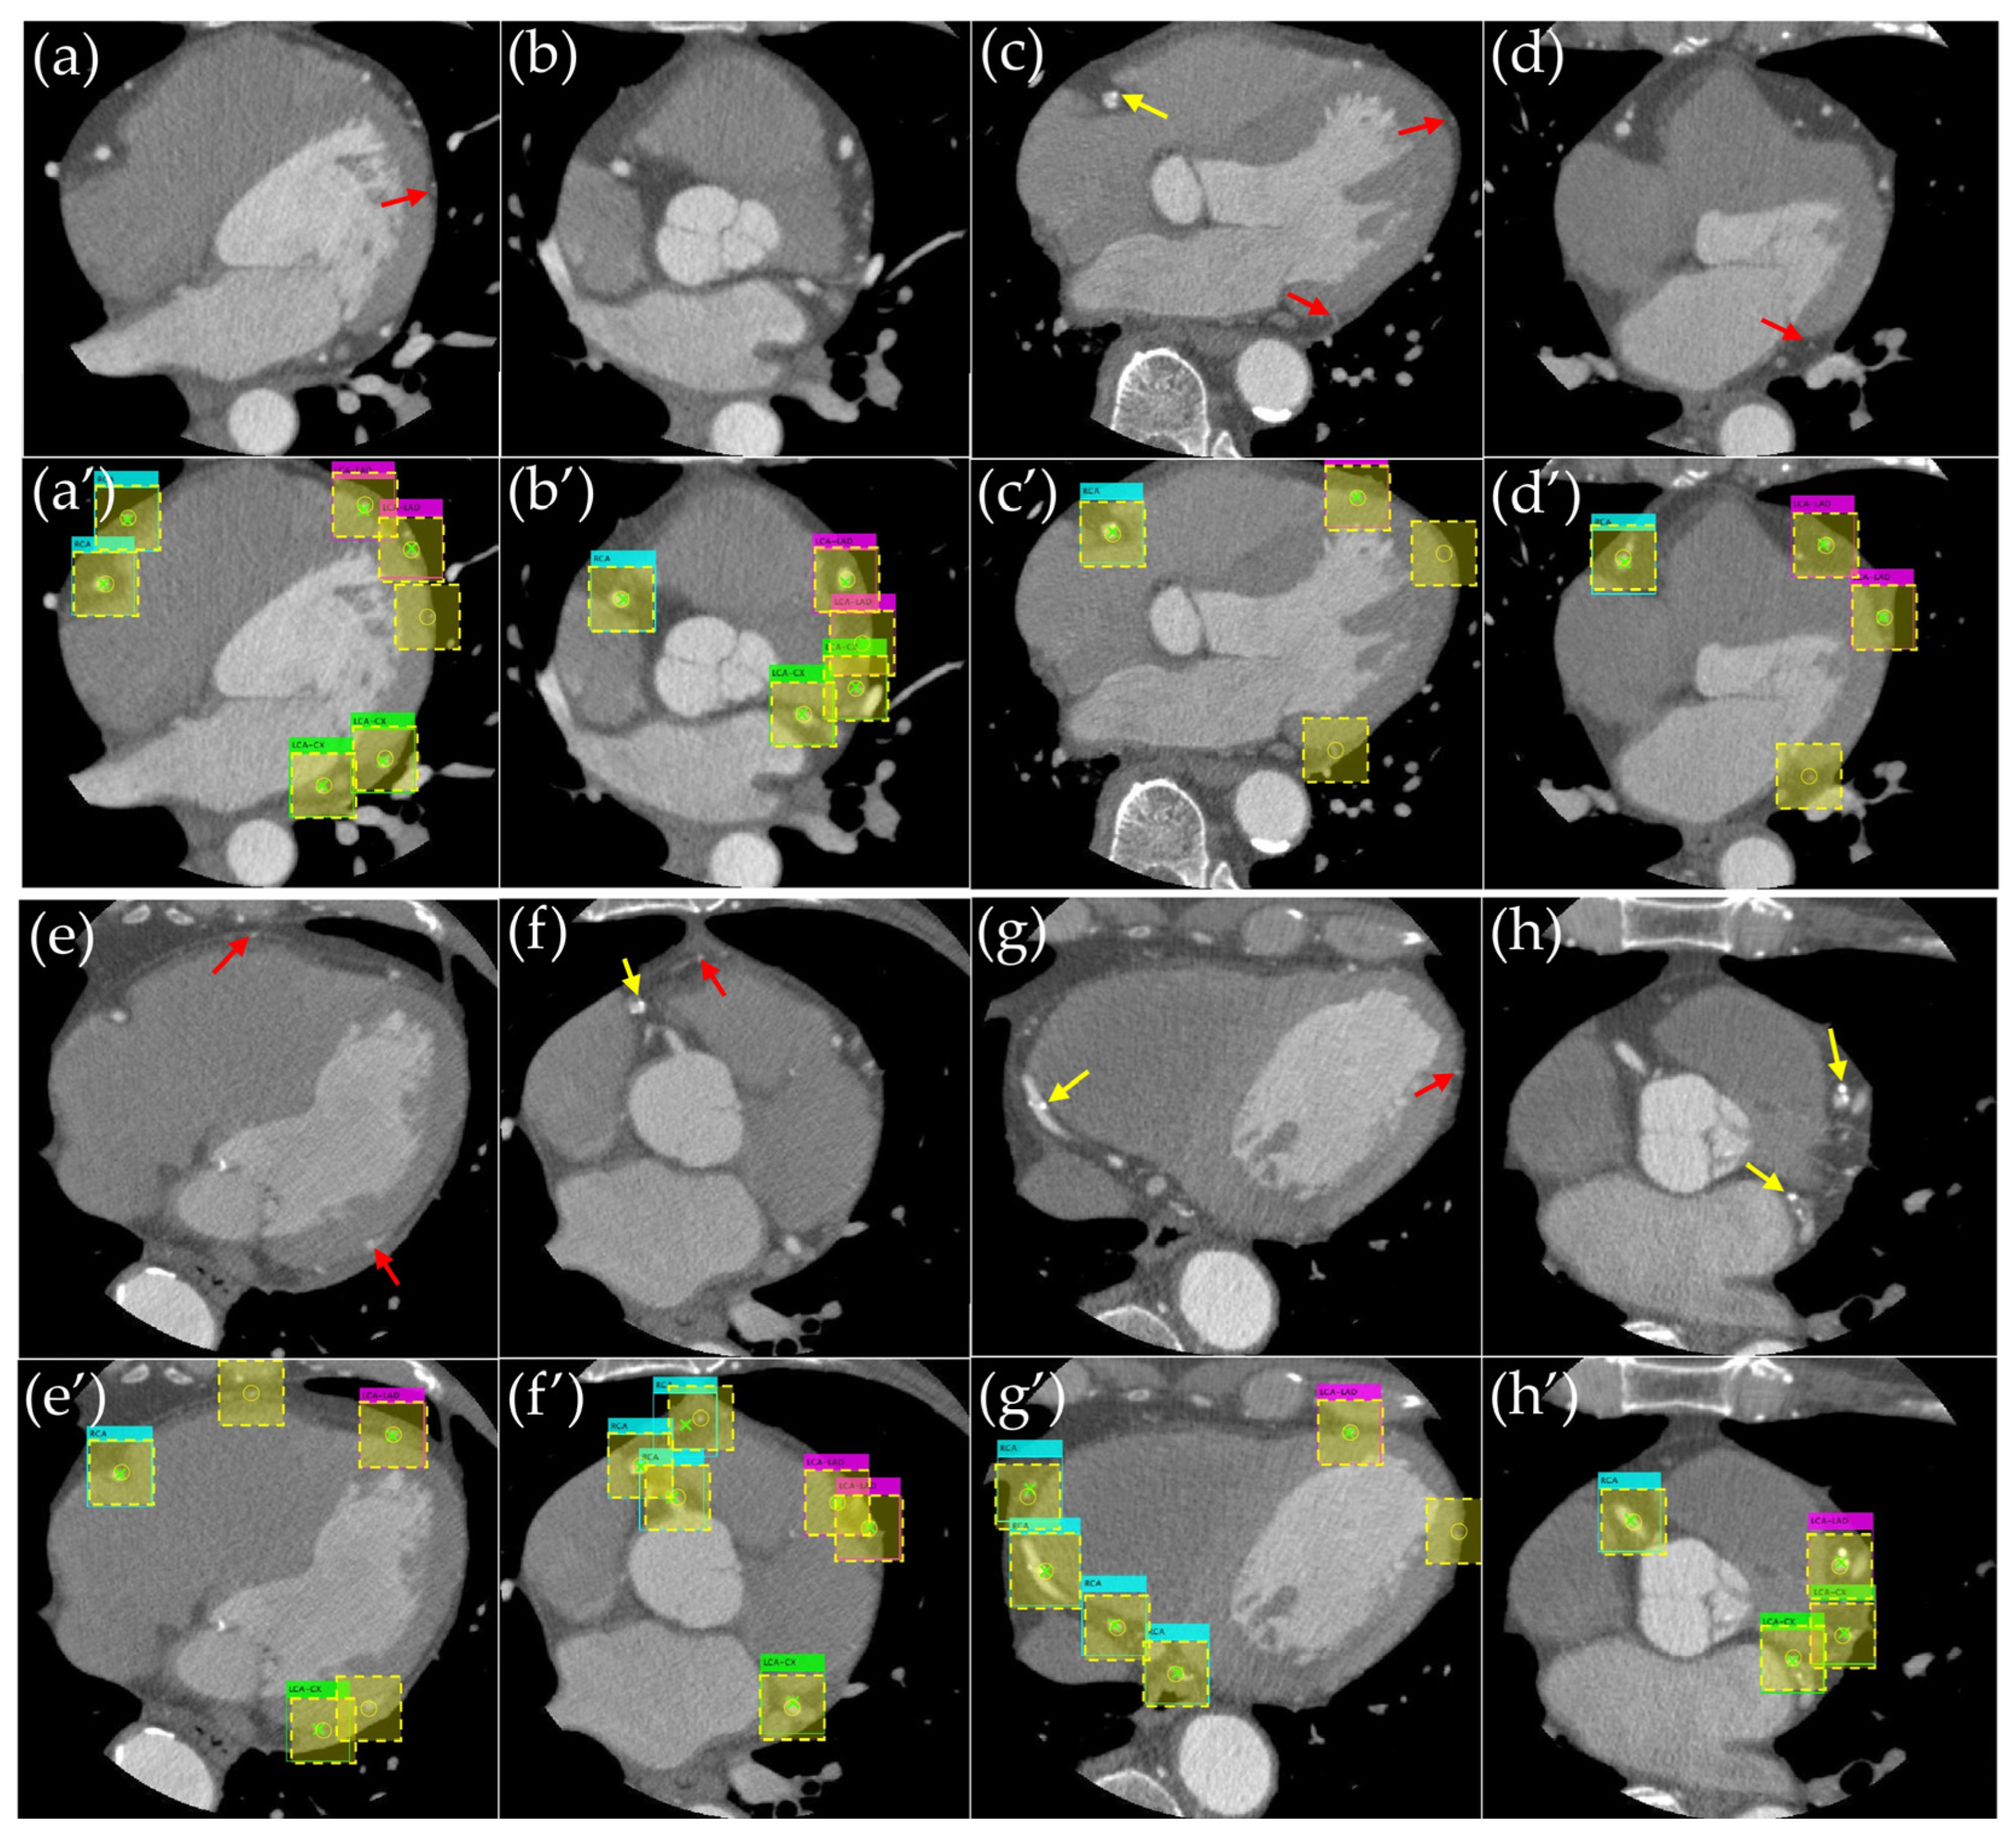

3.1. Evaluation of the Object Detection Model

3.2. Evaluation of Detection Accuracy Using Additional Metrics

4. Discussion